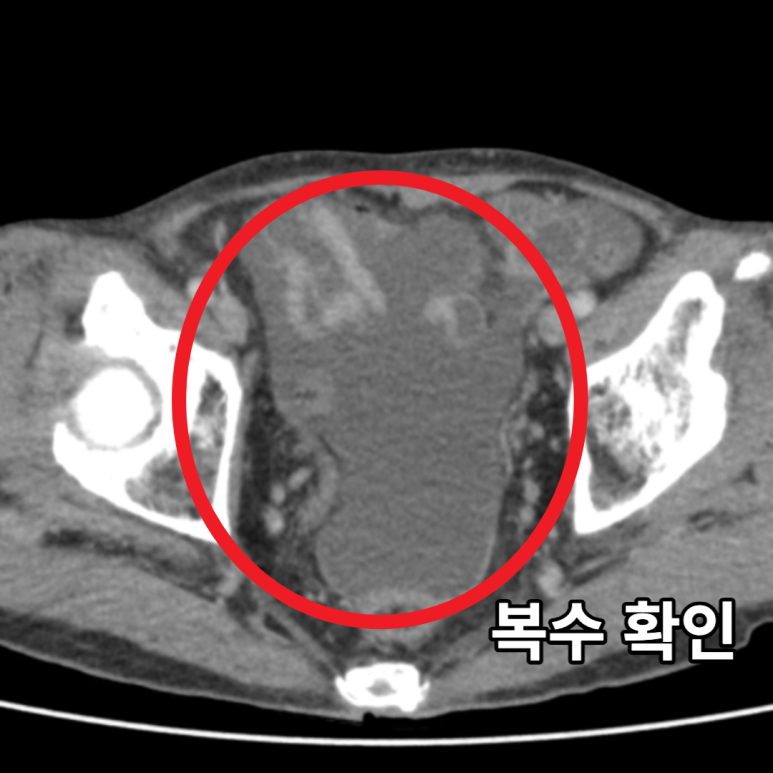

단순 소화불량처럼 보이는 명치 통증, 하지만 실제로는 췌장염, 담도염, 위궤양, 심지어 대동맥 박리까지 생명을 위협하는 질환의 신호일 수 있습니다. 특히 고혈압, 당뇨병, 고지혈증, 담석, 음주 습관 같은 기저질환이 있는 경우, 이 통증은 더 이상 가볍게 여겨선 안 됩니다.